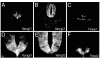

Neural tube defects (NTDs) are very frequent congenital abnormalities in humans. Recently, we have documented independent association of Vangl1 and Vangl2 gene mutations with NTDs. In the Looptail mouse, homozygosity (but not heterozygosity) for loss-of-function alleles at Vangl2 causes the severe NTD craniorachischisis, whereas heterozygosity for mutant variants of VANGL1 is associated with NTDs in a human cohort of sporadic and familial cases. To understand the role of Vangl1 in normal development, we created a mouse mutant with an inactivating mutation at Vangl1 (Vangl1(gt)). Vangl1 shows a dynamic pattern of expression in the developing neural tube and notochord at the time of neural tube closure. Vangl1(gt/+) heterozygotes and Vangl1(gt/gt) homozygotes are viable and fertile, although Vangl1(gt/gt) display subtle alterations in polarity of inner hair cells of the cochlea. Remarkably, and as opposed to healthy Vangl1(gt/+) and Vangl2(lp/+) heterozygotes, Vangl1(gt/+);Vangl2(lp/+) double heterozygotes show profound developmental defects that include severe craniorachischisis, inner ear defects (disorganization of the stereociliary bundles of hair cells of the organ of Corti), and cardiac abnormality (aberrant right subclavian artery). These results show that genetic interaction between Vangl1 and Vangl2 genes causes neural tube defects and raise the possibility that interaction between individual Vangl genes and other genetic loci and/or environmental factors may additionally contribute to the etiology of NTDs.